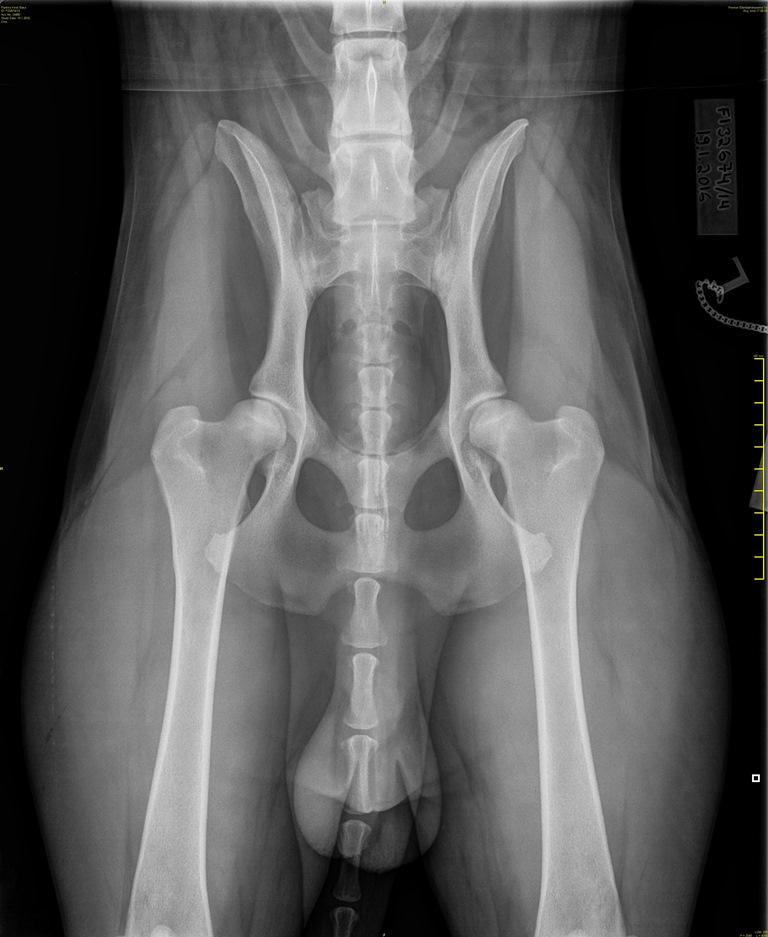

Bakari's hip X-ray